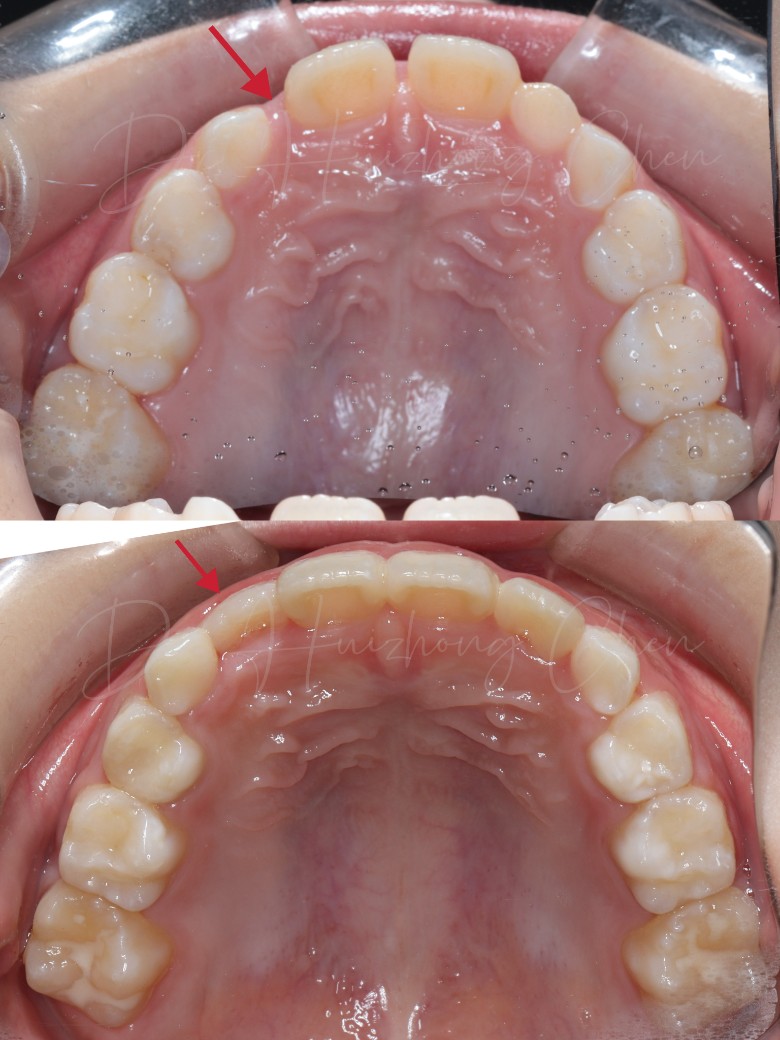

前面戴了不到一年的牙套吧,改善的还不错, 中场休息戴一段时间的保持器等换几颗牙再开始下一步方案,没空长牙的间隙肉眼可见的拉出来了,长歪的牙也拉的正正的了熊孩子配合的也不错,一天到晚除了吃饭都乖乖戴着,戴了这么久只丢过一副牙套,唯一的槽点就是刷牙太敷衍了,每次去都要被医生教育一下刷牙认真认真再认真点

还是蛮整齐的

现在看着蛮整齐的